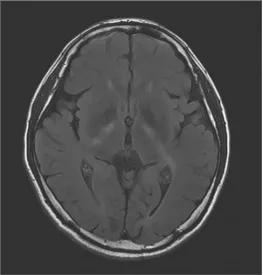

颅脑MRI提示双侧内囊膝、双侧内囊后肢、双侧大脑脚、脑桥和小脑齿状核处有对称的异常信号:

据报道,颅脑MRI中出现小脑齿状核异常信号可能是CTX的特异性表现。